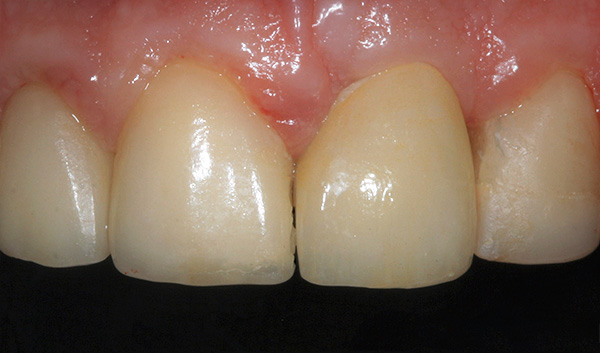

O resultado final das próteses usando uma coroa totalmente em cerâmica: